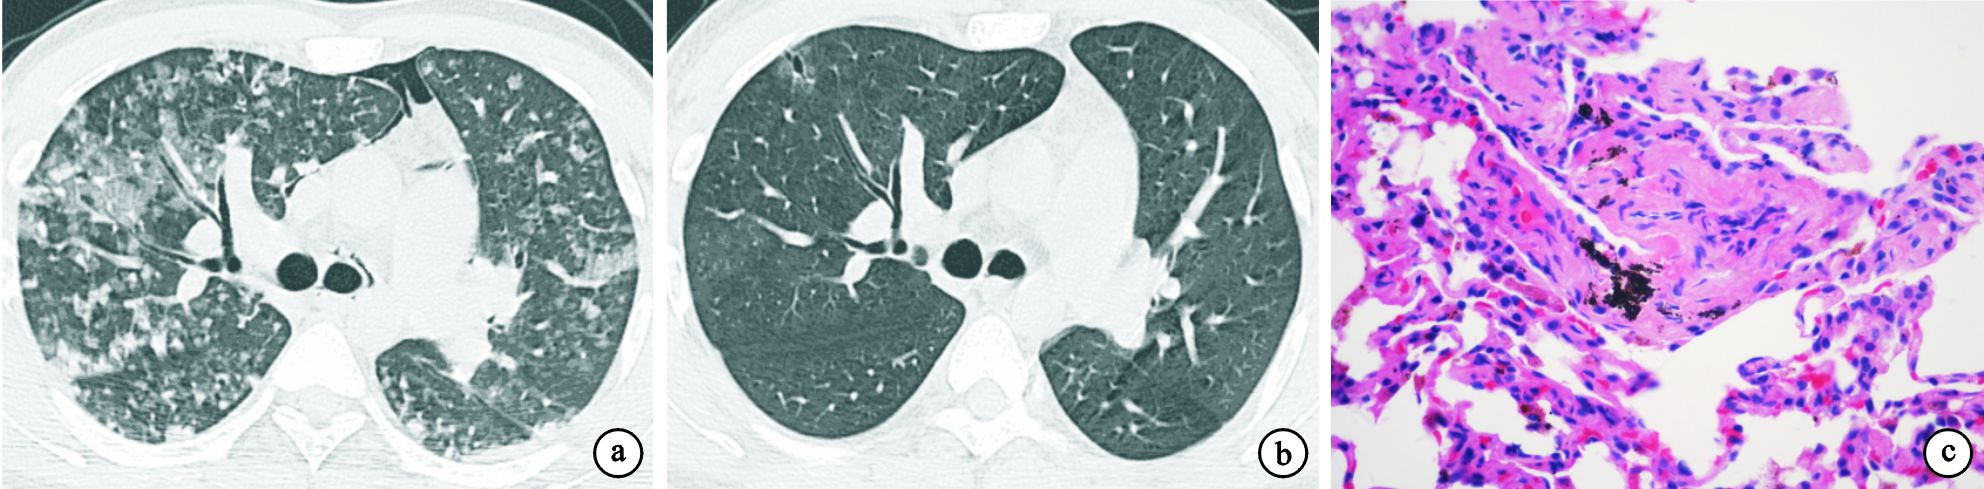

24例患者的主要胸部HRCT特征總結見表 1。17例(70.8%)雙肺彌漫分布磨玻璃影,多呈斑片或片狀;15例(62.5%)雙肺彌漫分布細支氣管或小葉中心結節,邊緣模糊;10例(41.7%)氣體陷閉或馬賽克征;5例(20.8%)有網格影或伴蜂窩肺。上述改變常重疊存在,磨玻璃影伴馬賽克征10例,小葉中心結節影伴馬賽克征9例,磨玻璃影、小葉中心結節伴馬賽克征7例,彌漫磨玻璃影伴實變影4例,網格影或伴蜂窩肺伴磨玻璃影2例。2例急性患者分別表現為彌漫磨玻璃影伴實變影(圖 1a、圖 2a),脫離暴露因素并給予甲基潑尼松龍靜滴,后改為潑尼松治療后,3周內病變明顯吸收(圖 1b、圖 2b)。17例亞急性患者中14例(82.4%)為彌漫分布的小葉中心結節(圖 3a、圖 4a),3例(76.5%)為磨玻璃影,8例(47.1%)為馬賽克征,8例(47.1%)為彌漫分布的斑片磨玻璃影伴馬賽克征。脫離暴露因素并給予潑尼松治療后病變均明顯吸收(圖 3b、圖 4b)。5例慢性患者均表現為網格影或伴蜂窩肺(圖 5a),其中2例伴斑片磨玻璃影,1例伴馬賽克征,1例伴小葉中心結節。

急性期2例行TBLB檢查,病理為肺泡壁和細支氣管壁水腫,以淋巴細胞性肺泡和間質炎癥為主,而嗜酸粒細胞浸潤較少。肺泡腔內有蛋白滲出及炎癥細胞(圖 1c、圖 2c)。亞急性期17例均行TBLB病理檢查,其中11例間質中見非干酪性壞死肉芽腫(圖 3c),其對應的HRCT表現為典型的小葉中心結節,另6例見單核細胞浸潤所致的細支氣管炎(圖 4c)。慢性期5例中有1例開胸肺活檢,病理見纖維化及成纖維細胞灶(圖 5c),其對應的HRCT表現為網格影伴蜂窩肺或牽拉性支氣管擴張(圖 5a)。1例因急性加重死亡,其余3例行BALF檢查。22例(2例急性,17例亞急性,3例慢性)BALF檢查提示肺泡淋巴細胞滲出為主的炎癥,巨噬細胞(31.5±18.3)%,淋巴細胞(36.4±19.7)%,中性粒細胞(22.4±18.5)%,嗜酸粒細胞中位數為2.3%(0.5%~4.5%)。CD4/CD8 T淋巴細胞比值中位數為0.96(0.48~1.61)。